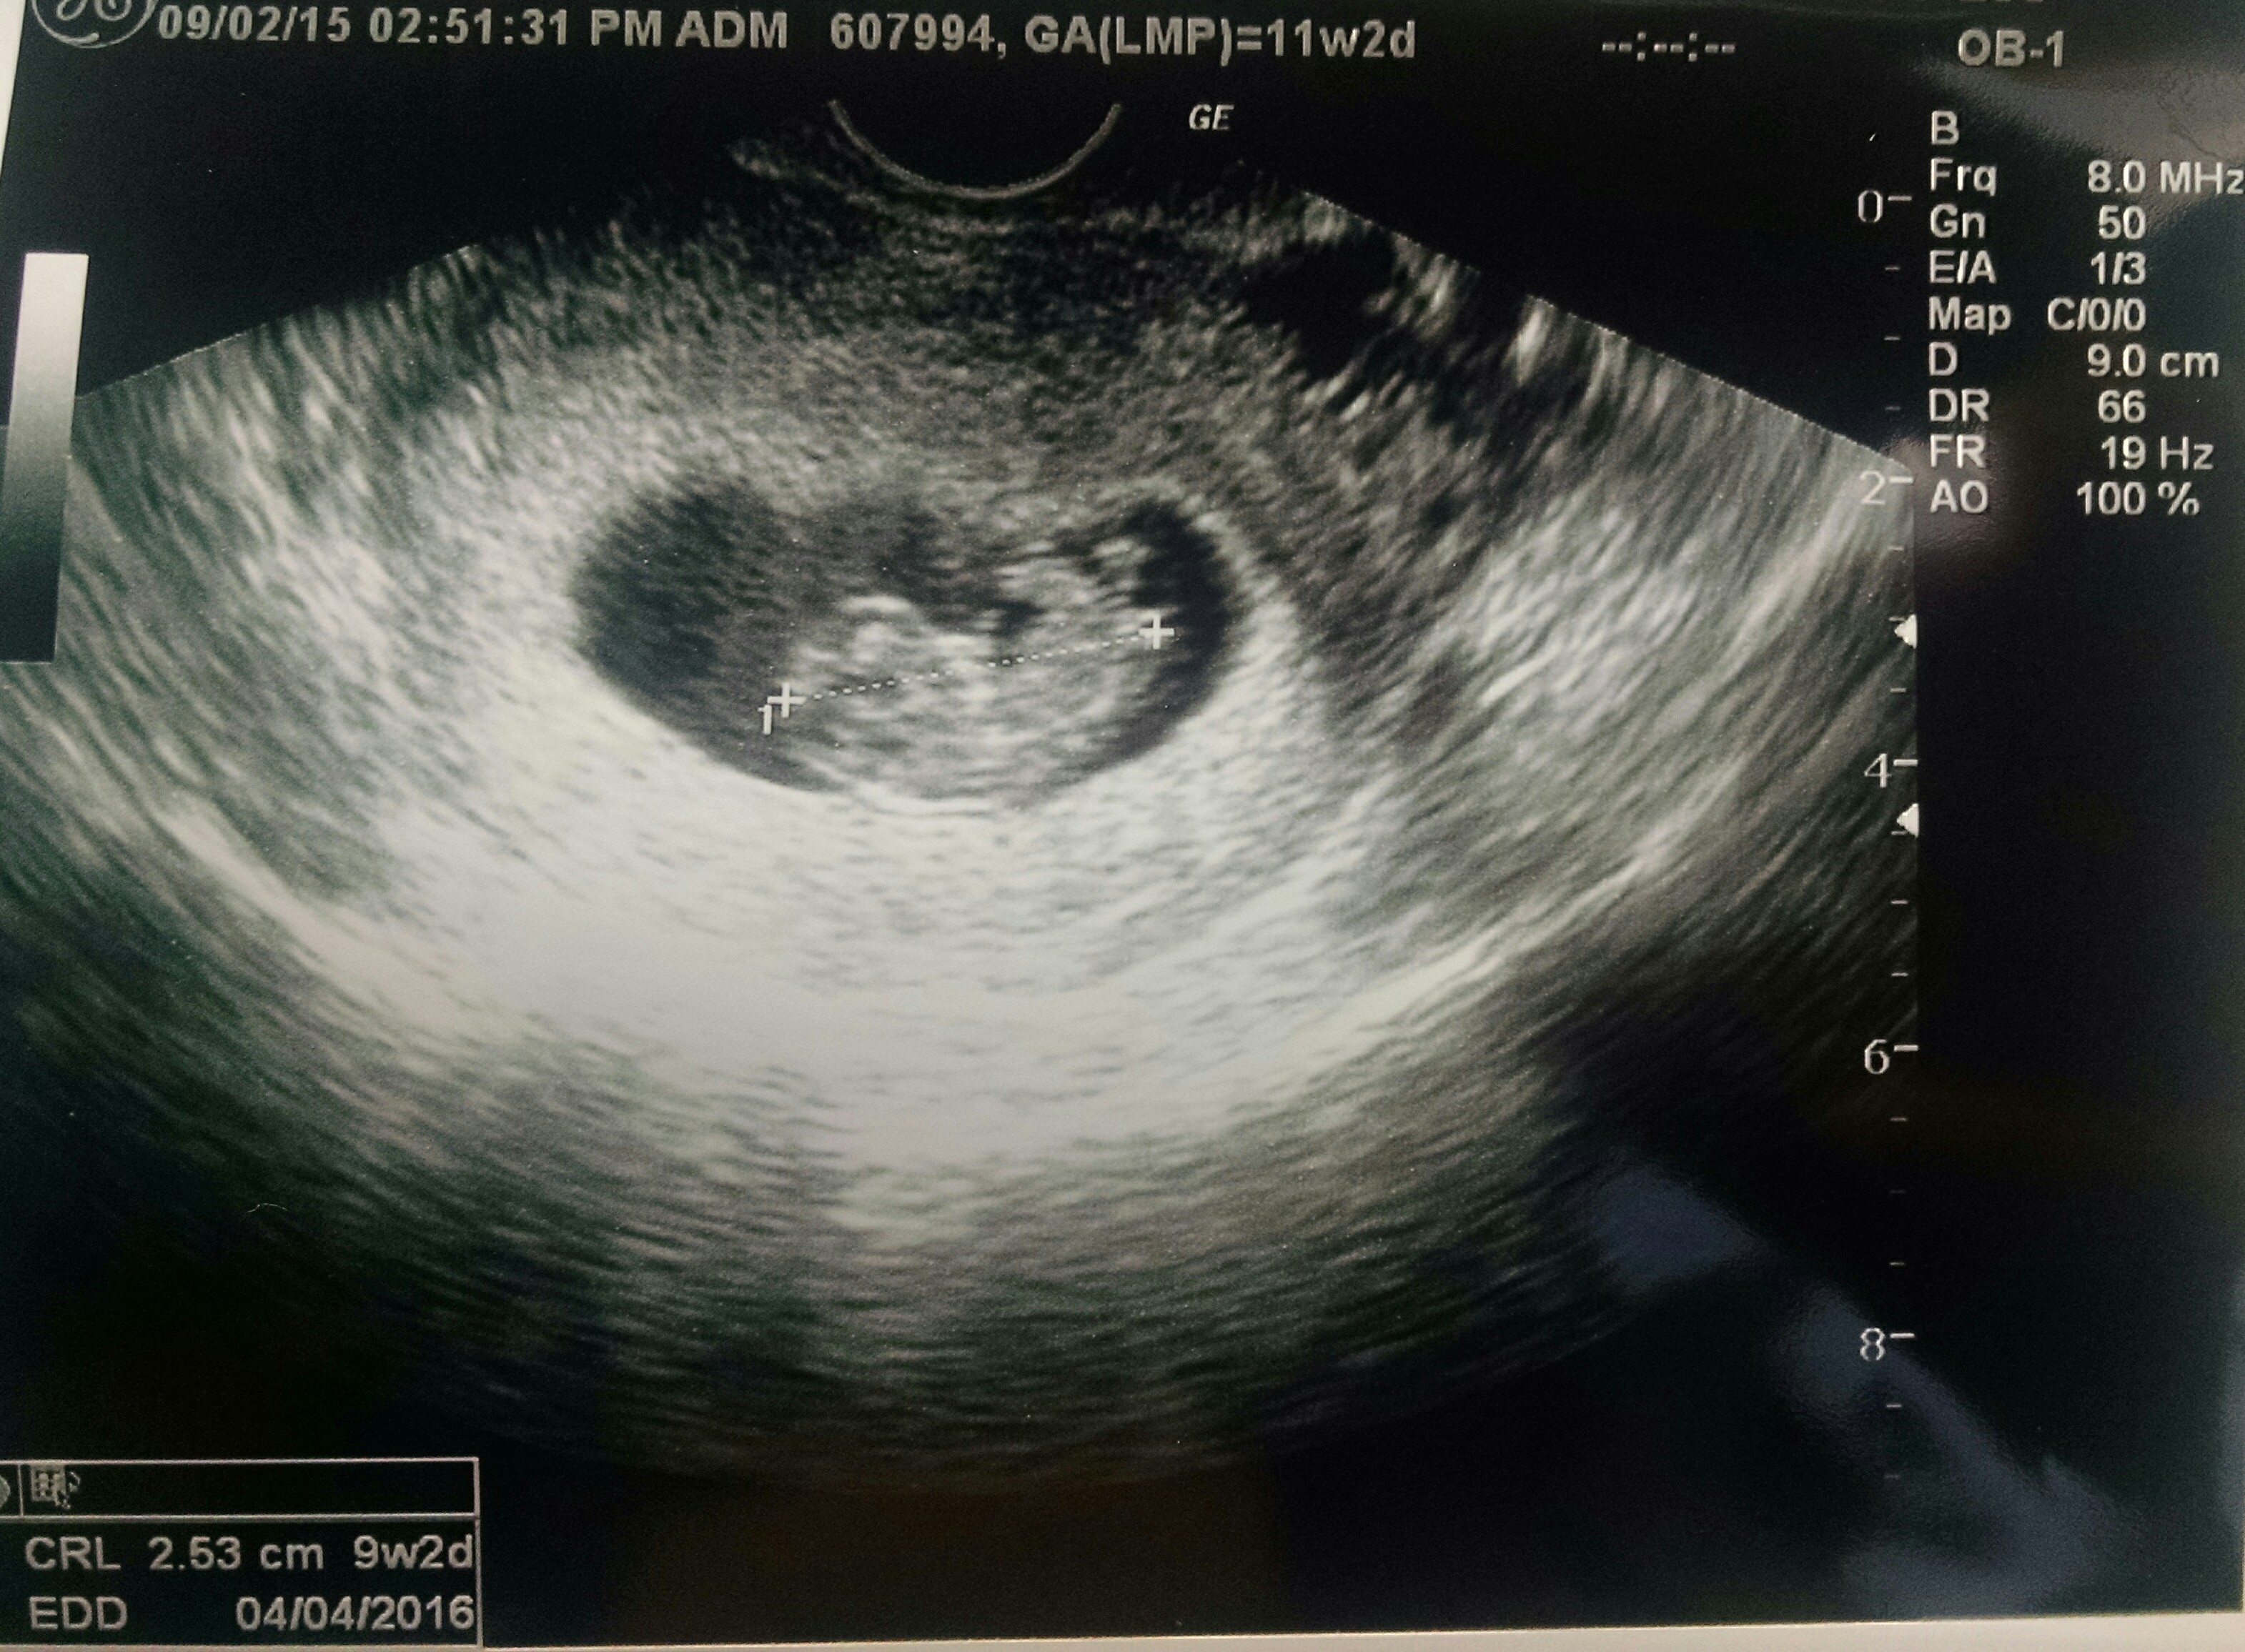

Had an unexpected US today due to some cramping. I was so expecting the worst... I am my own worst enemy but, baby has once again doubled in size from last Friday 8.21.15 to today 8.28.15!! Heartbeat today was up from 165 to 182!!!! We also got to see he/she wiggle which brought tears to my fiancées eyes... And in turn I cried. Tears of joy!! Keeping all of you in my thoughts! Positive vibes your way!